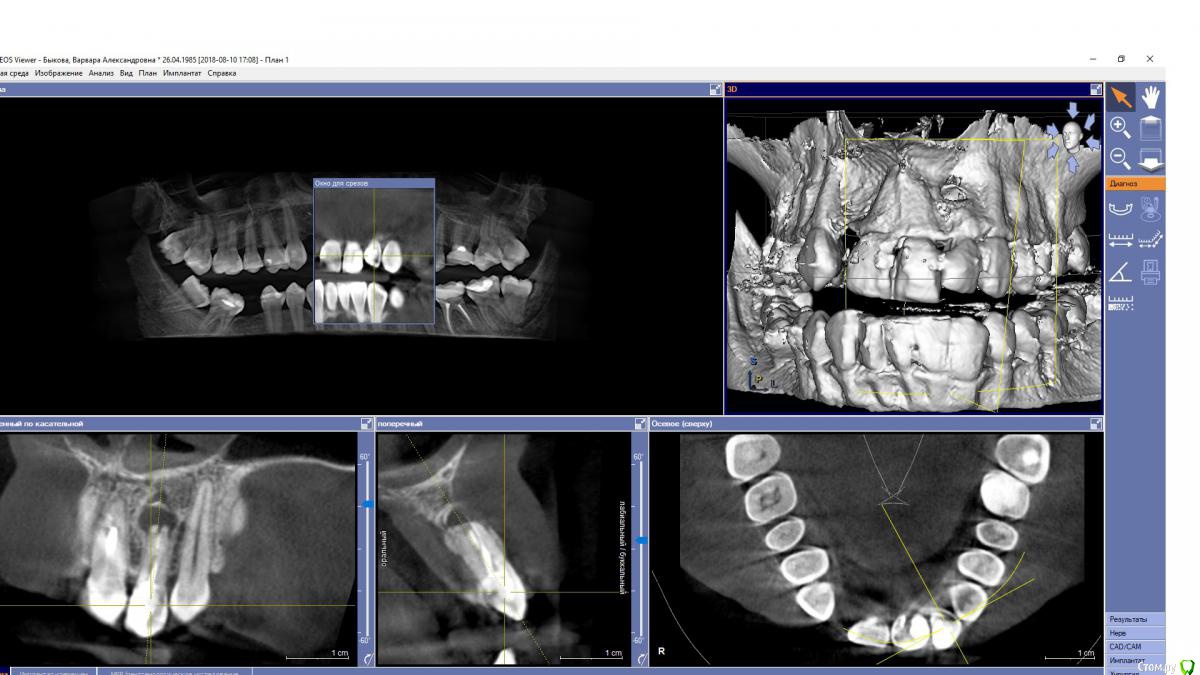

EEcho Опубликовано 27 августа, 2018 Поделиться Опубликовано 27 августа, 2018 Варианты решения данной ситуации?Пациентка хочет импланты, но не хочет обращатся к ортодонту.Что посоветуете? Ссылка на комментарий

EEcho Опубликовано 29 августа, 2018 Автор Поделиться Опубликовано 29 августа, 2018 22 у нее развернут, на 12 носит бабочку, развернутые двойки ее устраивают. к ортодонту категорически не хочет и не хочет точить свои зубы.На 22 еще и киста, планирую удалять 22. Ссылка на комментарий

Дмитрий Л. Опубликовано 30 августа, 2018 Поделиться Опубликовано 30 августа, 2018 22 недопломбирован, зачем удалять?Варианты решения данной ситуации?Пациентка хочет импланты, но не хочет обращатся к ортодонту.Что посоветуете?Ключевая фраза: пациентка хочет импланты.Консоль +1 Ссылка на комментарий